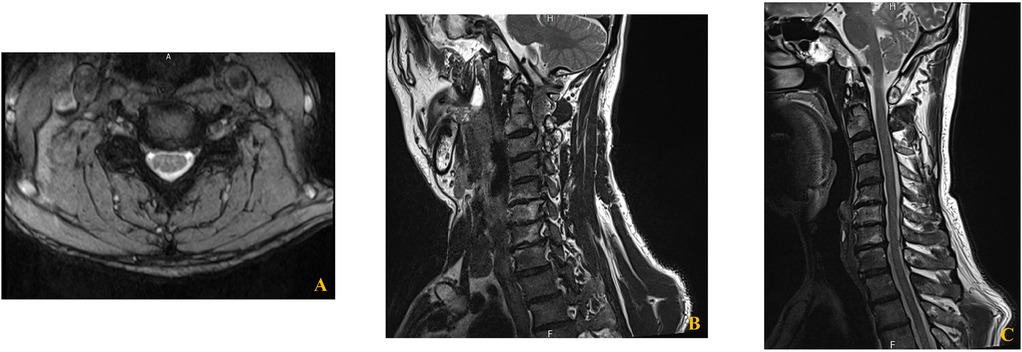

Over a five-week period, the patient received four epidural steroid injections under C-arm fluoroscopic guidance. The interlaminar approach was performed at the C6–7 level using a paramedian technique, directing the needle toward the right side for optimal drug delivery. The transforaminal approach targeted the right C6 nerve root by advancing the needle toward the C5/6 intervertebral foramen (Figure 2). Each injection consisted of dexamethasone palmitate (4 mg) (13), hyaluronidase (1,500 IU) (14), and 0.1% lidocaine (5 mL) (15). The patient was evaluated at regular intervals (4 days, 2 weeks, 4 weeks, and 5 weeks), with assessments of motor strength, shoulder ROM, and subjective symptom improvement. The clinical course, including changes in muscle strength and range of motion, is summarized in Table 1.

Figure 2

Fluoroscopic images of C6 cervical transforaminal epidural steroid injection. (A,B) Anteroposterior (A) and oblique (B) views of the second injection showing needle placement and contrast spread at the C6 neural foramen. (C,D) Anteroposterior (C) and oblique (D) views of the third injection demonstrating proper needle positioning and contrast distribution along the C6 nerve root pathway.